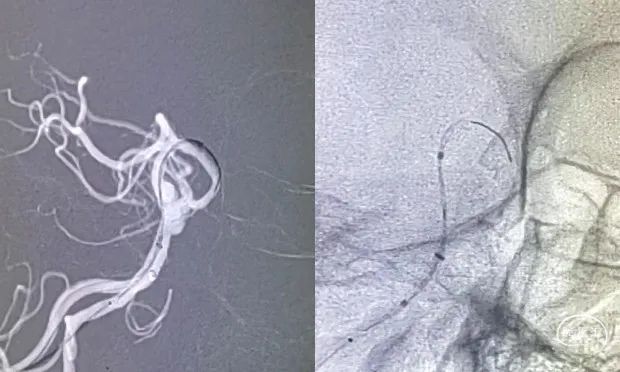

Fastrack支架导管顺中间导管在Traxcess微导丝导引下,顺利通过瘤体到达左侧大脑后动脉P3段,位置满意后撤出微导丝。

3

输送Tubridge®血流导向密网支架:支架导管逐渐后撤,支架头端部分送出支架导管,将头端锚定于基底动脉小脑上动脉开口下,逐渐缓慢释放支架,使支架充分打开,并顺利跨瘤颈到达动脉瘤流入道,完整释放支架。

释放支架:3.5mm*30mm Tubridge®血流导向密网支架缓慢释放,Tubridge®血流导向密网支架中点mark稳稳的定位在动脉瘤瘤颈处,蒙片显示支架位置良好,打开完全。

4